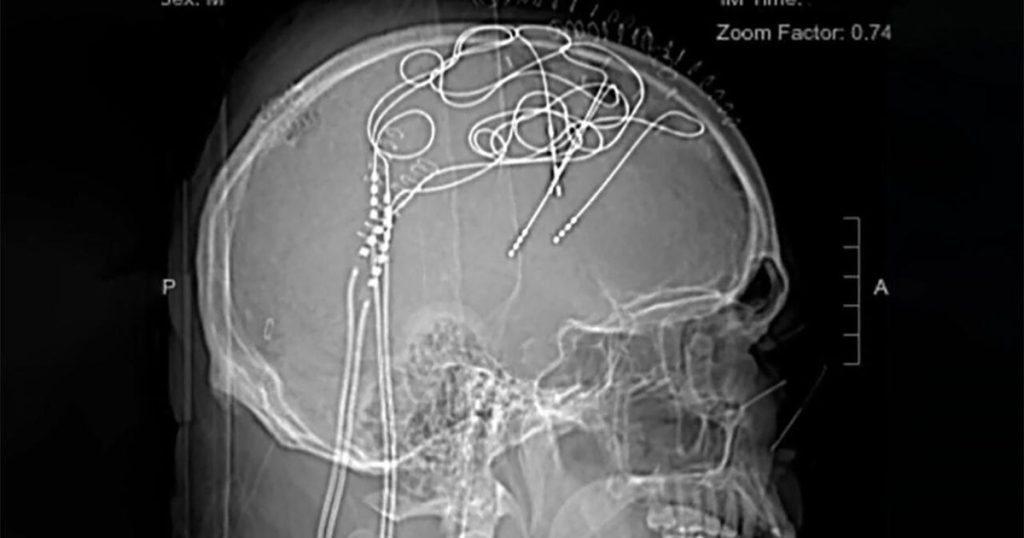

Mowery had volunteered for a study in deep brain stimulation and pain, and three rounds of brain surgery. “I had nodes sticking out of my head,” Mowery said. “And I had 144 wires going to two computers. And I had a turban on my head. And I also had a lot more hair!”

ed-mowery-brain-implants-ucsf.jpg

Researchers implanted electrodes into Ed Mowery’s brain, which helped identify brain areas and neural signals linked to his pain.

UCSF

Gupta said, “After weeks they were able to draw this link between Ed’s pain and these changes in the brain. And what they found with Ed was not only could they start to predict that Ed was gonna have pain, they could quantify how bad that pain was likely to be, and they could even interrupt the pain by giving a little stimulation. So even before the pain would get to conscious awareness, the stimulator would go off and it would start to interrupt that pain cycle.”

Gupta predicts Mowery’s story is just the beginning: “What these doctors were able to do, they were essentially able to put these probes all over the brain and just leave these probes in sort of to listen to Ed’s brain.”

Even now, a computer can recognize his pain coming on – and shut it off.